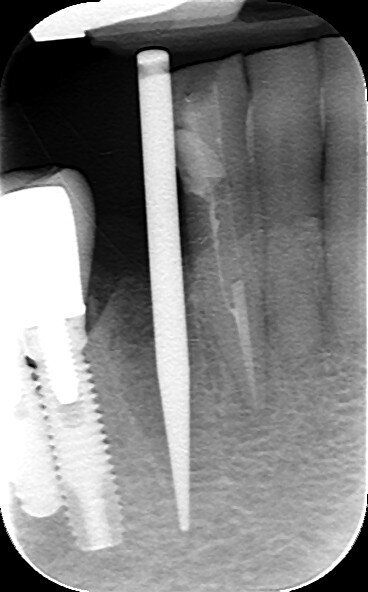

In particolare la perforazione del solco guida all’interno dell’alveolo è stata realizzata attraverso l’inserto IM1 AL, sulla superficie linguale dell’alveolo in direzione linguale. Successivamente l’inserimento del corrispondente perno indicatore conico-cilindrico e un esame radiografico endorale ci hanno consentito di verificare l’asse della preparazione e l’eventuale vicinanza con le radici dei denti vicini (Figg. 6-8). In questi casi, infatti, secondo quello che da un punto di vista tecnico, rappresenta il valore aggiunto della procedura, è possibile la correzione immediata dell’asse inserendo nuovamente l’inserto IM1 AL, senza rischiare la compromissione della preparazione come accade spesso nei casi di utilizzo iniziale delle frese a spirale da 2 mm, dove le possibilità di correzione dell’asse sono minime. L’osteotomia è stata successivamente completata con l’inserto IM2 fino alla lunghezza determinata e con una fresa a spirale conica corrispondente all’impianto programmato.

Fig. 6

Fig. 7

Fgi. 8